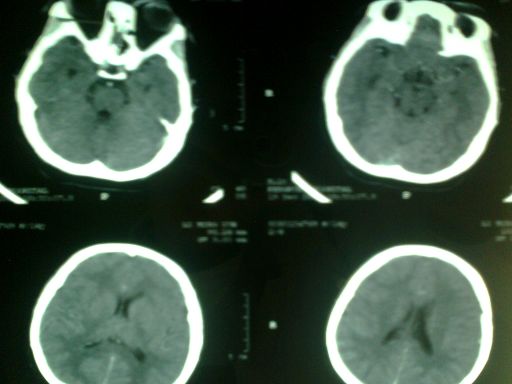

以下是引用dyqct在2008-12-20 16:16:00的发言:[br]查一下血红蛋白。长期缺氧引起血蛋白明显升高,可造成血管内血液密度增高。